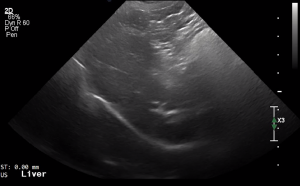

SIMON Ultrasound Database

This ultrasound database is a free resource for students and doctors!

Our collection includes videos of dogs, cats, horses, cows, humans, and many other species!

–Canine and Feline abdominal ultrasound videos were generously provided by the Cummings School of Veterinary Medicine at Tufts University.